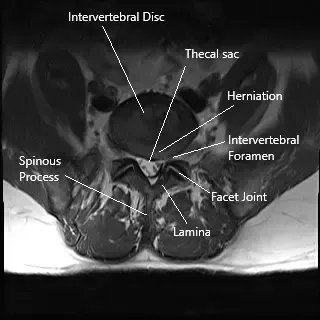

The lumbar spine consists of five vertebrae (L1 to L5) that support the lower back. The spinal cord passes through the spinal canal, and nerves branch out from the spinal cord, exiting through foramina to provide sensation and motor function to the lower extremities. The lamina forms part of the roof of the spinal canal, protecting the spinal cord and nerves.

- MRI or CT Scan: To evaluate the spinal canal, identify herniated discs, bone spurs, or stenosis, and assess the extent of nerve compression.

Hemilaminectomy/laminotomy is a surgical procedure used to relieve pressure on the spinal cord and nerves. Unlike a full laminectomy, which involves removing a larger portion of the lamina (the roof of the spinal canal), a hemilaminectomy removes only a small part, making it less invasive.

Removal of Lamina: Using specialized instruments, the surgeon removes a portion of the lamina and may also remove parts of the thickened ligamentum flavum or herniated disc material.